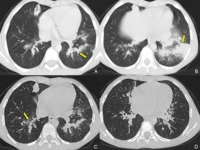

Bu belirtiler, lezyonun yerleşim yeri ve büyüklüğüne göre değişiklik gösterebilir. 4. Tanı YöntemleriYoğun içerikli kistik lezyonların tanısı, çeşitli görüntüleme yöntemleri ve biyopsi ile yapılabilir. Kullanılan başlıca tanı yöntemleri şunlardır:

Bu yöntemler, lezyonun özelliklerini, boyutunu ve içeriğini belirlemeye yardımcı olur. 5. Yoğun İçerikli Kistik Lezyonların TedavisiTedavi planı, lezyonun tipi, boyutu ve hastanın genel sağlık durumu gibi faktörlere bağlı olarak değişir. Yoğun içerikli kistik lezyonların tedavi seçenekleri arasında: